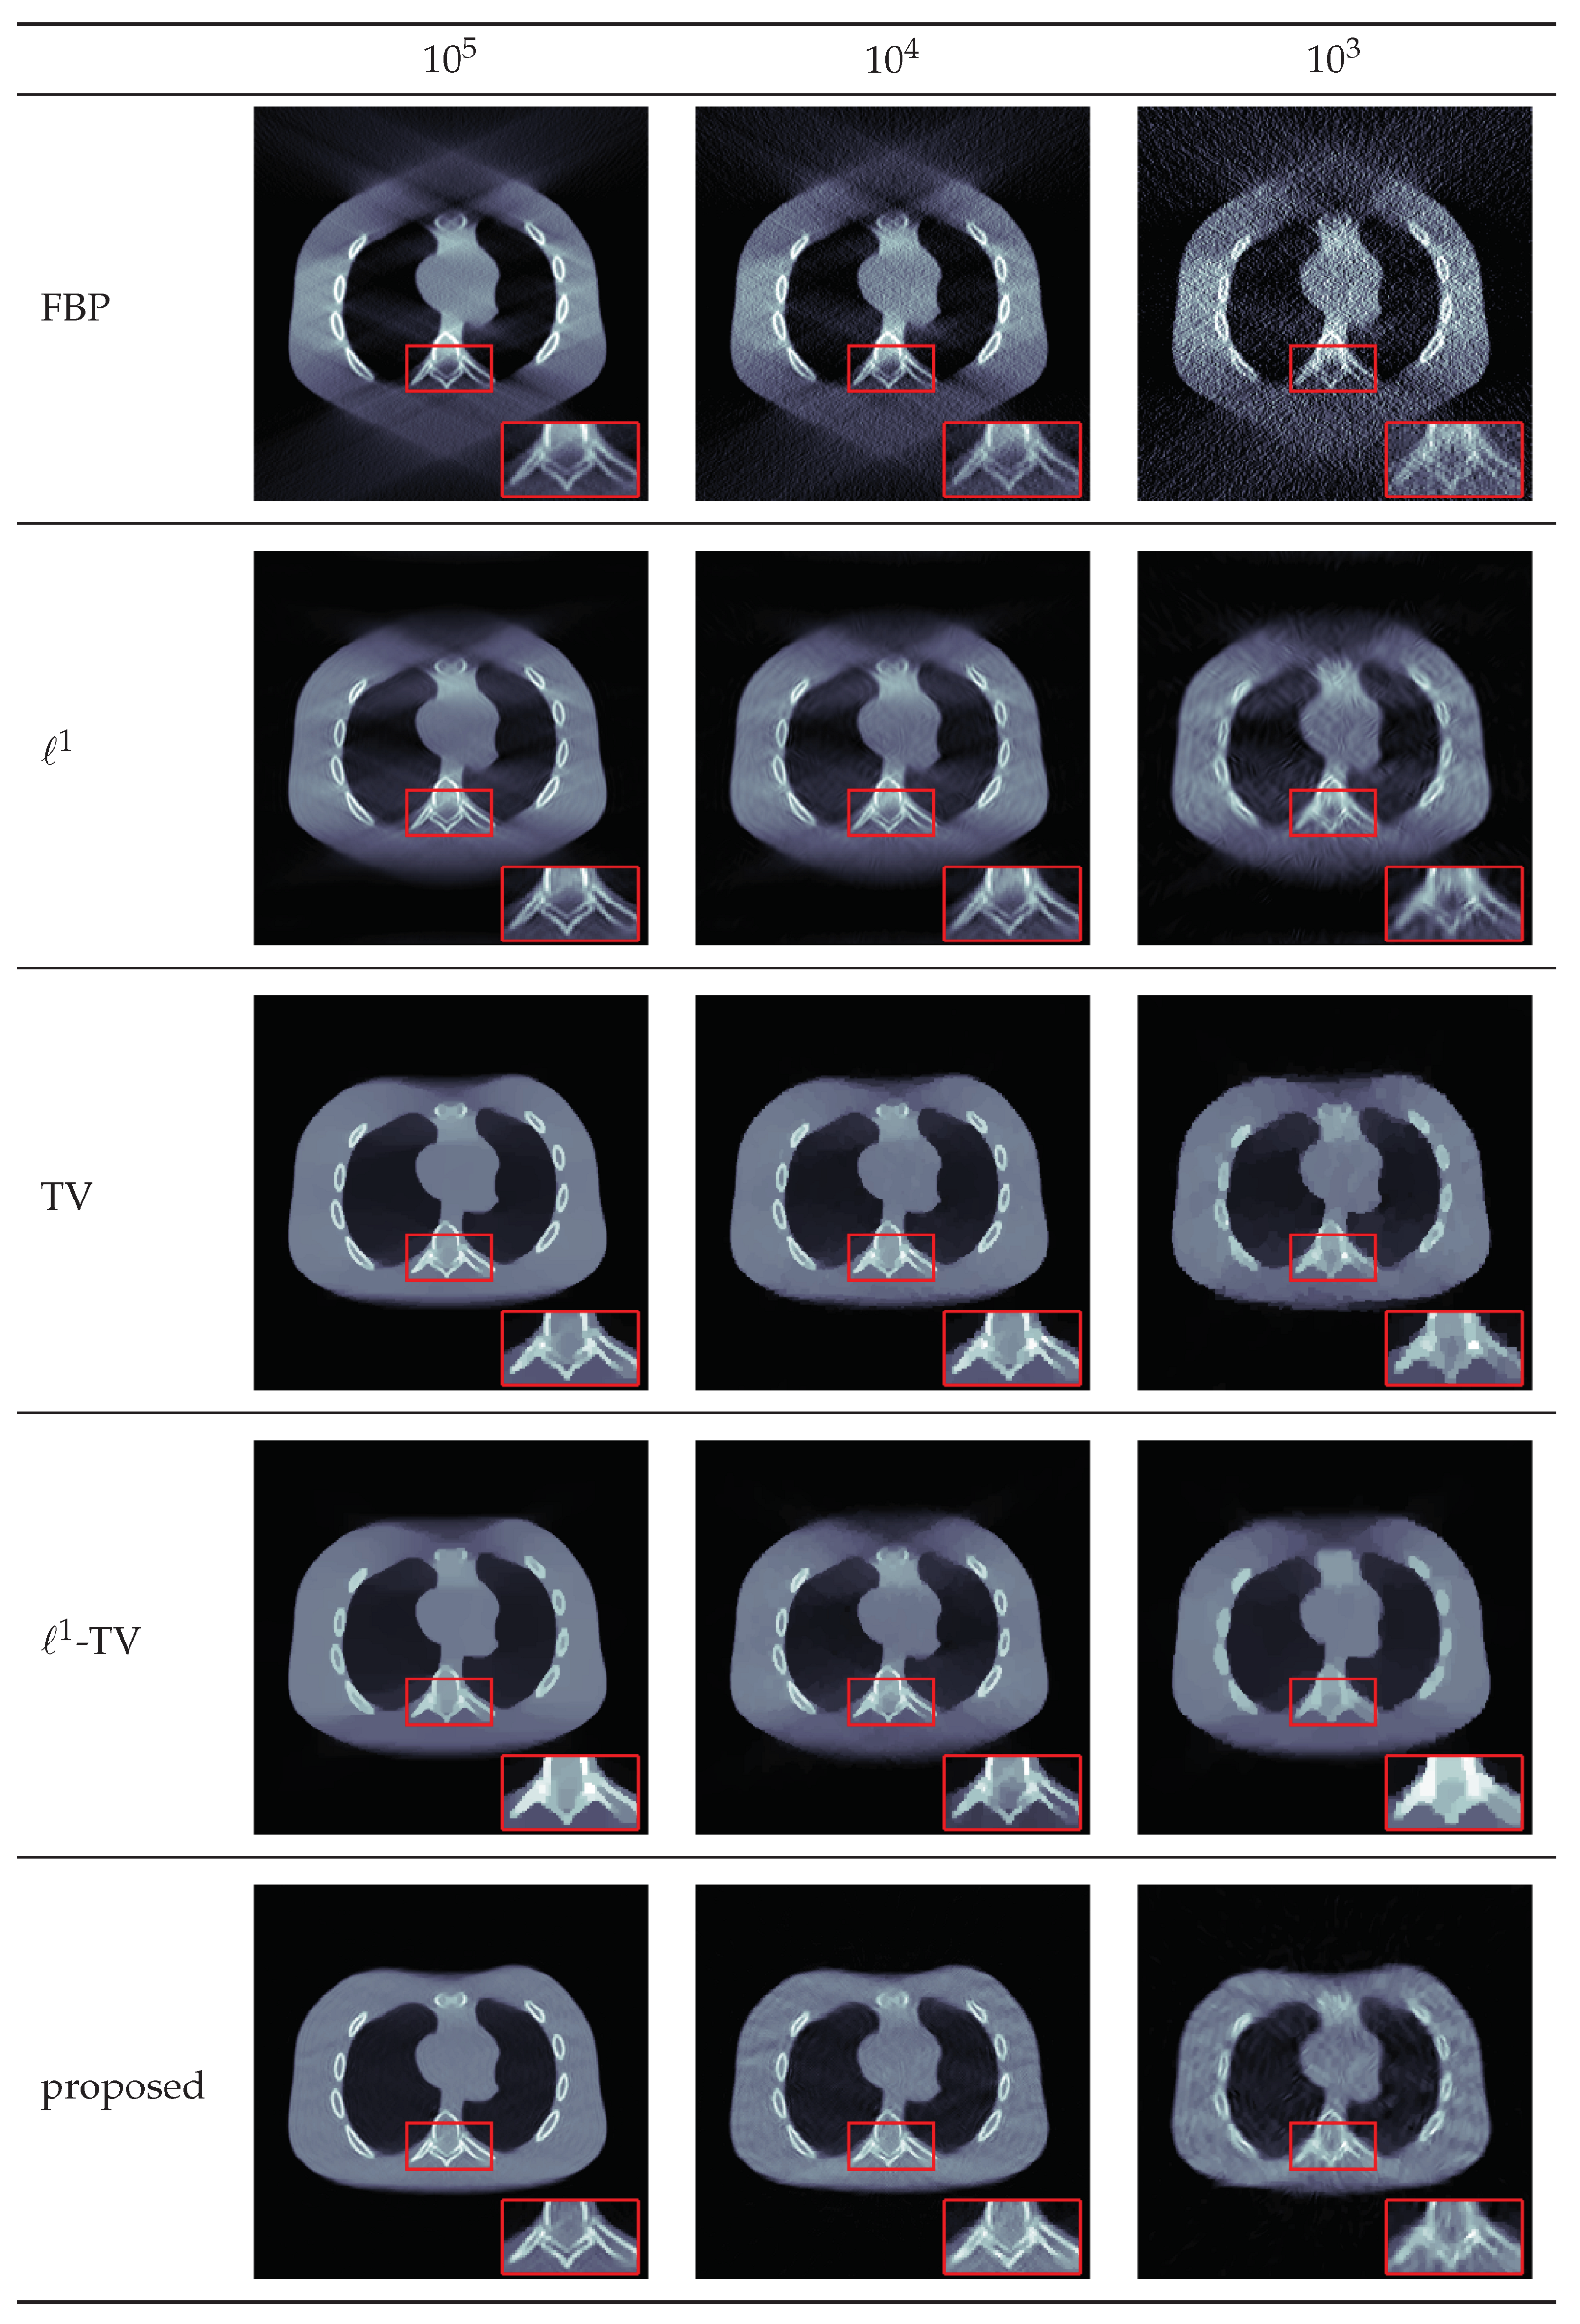

4.2. Results for Limited View Data

| # Photons | Method | PSNR | SSIM |

|---|---|---|---|

| FBP | 17.1021 | 0.2693 | |

| 22.590 | 0.559 | ||

| TV | 29.725 | 0.953 | |

| -TV | 25.4124 | 0.8540 | |

| proposed | 31.438 | 0.949 | |

| FBP | 16.7306 | 0.1635 | |

| 22.1291 | 0.5430 | ||

| TV | 27.1590 | 0.9210 | |

| -TV | 24.0859 | 0.7633 | |

| proposed | 29.0141 | 0.8815 | |

| FBP | 14.1189 | 0.0696 | |

| 21.4974 | 0.4328 | ||

| TV | 24.9321 | 0.8621 | |

| -TV | 23.7100 | 0.7898 | |

| proposed | 26.1420 | 0.7906 |